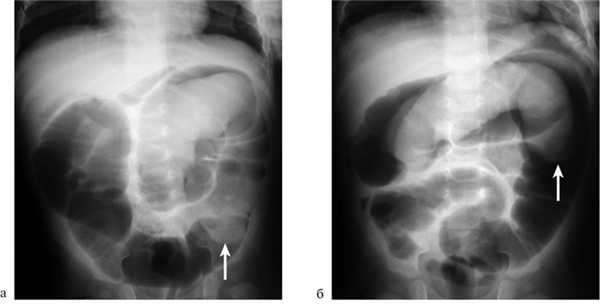

На рисунках 4 и 5 представлена картина кишечной инвагинации при рентгенологическом исследовании.

Рис. 4. Ирригограмма при тугом наполнении взвесью сульфата бария - симптом «клешней рака»

Рис. 5. Ирригограмма после опорожнения толстой кишки - симптом «кокарды»